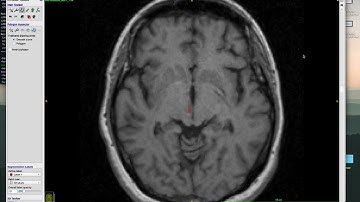

Tutorial - Cutting a chimpanzee brain stem in ITKSNAP